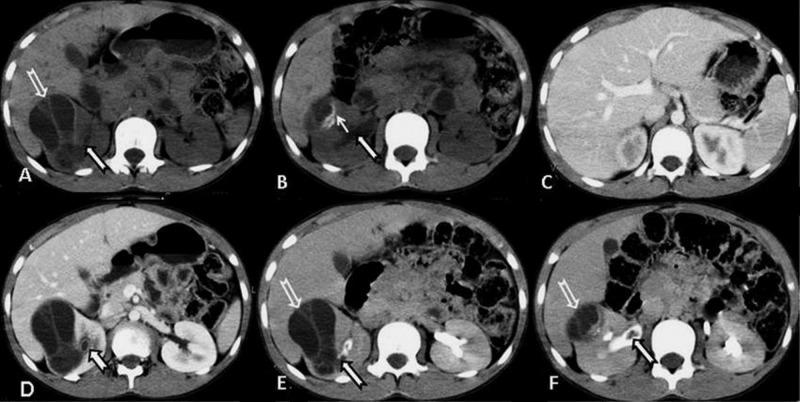

Objective The objective of this study was to assess various locations in the abdomen wherein hydatid cysts can occur in an Indian population. Materials and methods A retrospective study was conducted on 38 patients of 20-55 years of age in an Indian population, who were diagnosed with hydatidosis on ultrasound and computed tomography. The measurement and location of the cysts were taken by the double operator method. Patients were followed up until post-surgical and histopathological diagnosis. Results Among the observed patients, the most common age group was 30-40 years (36.85%), with male predominance (76%). The most commonly involved organ was liver (71.1%) followed by the kidney (10.5%) and peritoneum (8%), pancreas (2.6%), spleen (2.6%), common bile duct (2.6%) and adnexa (2.6%). Conclusion In spite of the usual presenting features, the locations of the cysts were unusual, thus warranting the importance of making the diagnosis before rupture of the cysts and thereby preventing life-threatening complications such as anaphylactic shock.

目的 本研究的目的是评估印度人群中可能发生包虫囊肿的腹部各个部位。材料与方法 对印度人群中38例年龄在20至55岁之间、经超声和计算机断层扫描诊断为包虫病的患者进行了回顾性研究。囊肿的测量和定位采用双人操作法。对患者进行随访直至术后及组织病理学诊断。结果 在观察的患者中,最常见的年龄组为30至40岁(36.85%),男性占优势(76%)。最常受累的器官是肝脏(71.1%),其次是肾脏(10.5%)、腹膜(8%)、胰腺(2.6%)、脾脏(2.6%)、胆总管(2.6%)和附件(2.6%)。结论 尽管有常见的表现特征,但囊肿的位置不寻常,因此有必要在囊肿破裂前进行诊断,从而预防诸如过敏性休克等危及生命的并发症。